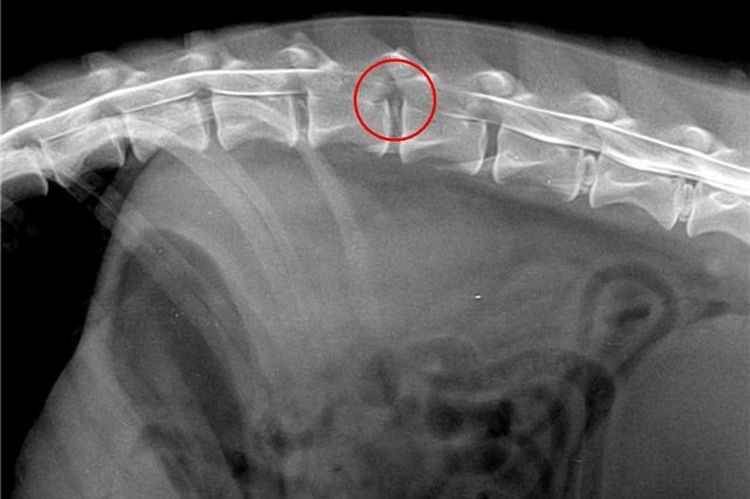

- Radiographie de la colonne vertébrale. Cet examen permettra de déterminer la zone touchée et l'étendue des lésions des tissus vertébraux et des disques intervertébraux. Les radiographies sont essentielles au diagnostic de la discopathie.

Les méthodes diagnostiques les plus informatives sont l'imagerie par résonance magnétique et la tomodensitométrie. Cependant, ces examens sont rarement pratiqués sur les animaux en raison de leur coût.